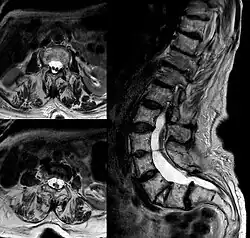

Bereits in einer Röntgen-Übersichtsaufnahme der Wirbelsäule können meist lumbal an den Wirbelkörpern, Bogenwurzeln oder dem Wirbelbogen Veränderungen sowie häufig knöcherne Spornbildungen erkannt werden.[8]

Eine detaillierte Darstellung auch knorpeliger Veränderungen gelingt zuverlässig mit der Kernspintomographie. Eine genaue Analyse des Duraschlauches ist mittels Myelographie, meist in Verbindung mit der Computertomographie (Myelo-CT) möglich.